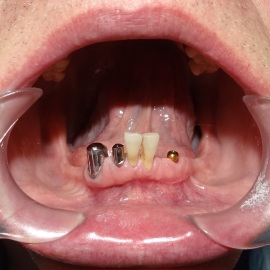

Pacjentka lat 72, od kilkudziesięciu lat chorująca na cukrzyce I typu, obecnie od 10 lat na pompie insulinowej. Profesor medycyny, siostrzenica pacjentki prowadzi swoją ciocię diabetologicznie, pacjentka świadoma zagrożeń przy zabiegach regeneracji kości i implantacji w takim ogólnym stanie zdrowia. Po rekonstrukcji tkanek miękkich i kości osadzono dwa implanty o średnicy 5,0 mm. Na zdjęciu śródzabiegowym widać zadowalające wyniki rekonstrukcji tkanki kostnej. Po upływie kilku miesięcy wykonano nadbudowę protetyczną.